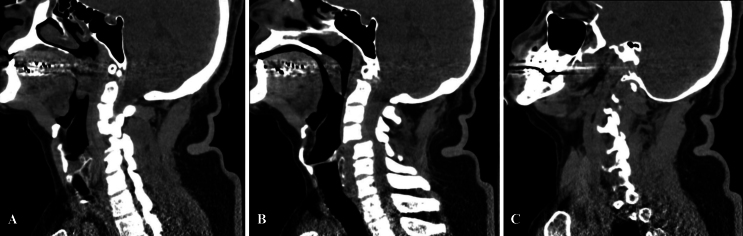

Background: Traumatic vertebral artery injury (TVAI) is a serious yet underdiagnosed complication of cervical spine trauma, with an incidence ranging from 0.1% to 3.2%. While its neurological sequelae vary, the risk of vertebrobasilar ischemia can be as high as 33.3%. The authors present a rare case of bilateral vertebral artery occlusion with concomitant basilar artery occlusion following C4-5 anterolisthesis.

Observations: The patient initially exhibited no clinical signs of vertebrobasilar ischemia. Diagnosis was achieved through vascular imaging, and successful endovascular thrombectomy with thrombus removal was performed. Unique to this case, manual cervical reduction was carried out in the endovascular suite while maintaining catheter placement in an effort to prevent recurrent dissection or emboli migration.